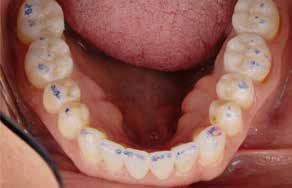

Der planlægges alignerbehandling af begge kæber med intrusion af 1+1 og 2,1-1,2, nivellering af trangstilling UK med interproksimal reduktion (IPR) (Fig. 2 A, B) og senere IPR OK for reduktion af dark triangles mellem incisiverne efter nivellering. Patienten instrueres i at benytte alignere 20-22 timer/ dag med alignerskift hver 7. dag, og patienten ses hver 3.-8. uge under forløbet. Den første alignerserie består af 16 alignere for nivellering OK/UK og IPR i UK (Fig. 2). Efter denne serie planlægges IPR mellem incisiverne i OK for reduktion af dark triangles (Fig. 3) samt yderligere intrusion af OK og UK-fronten i 12 refinement-alignere. Patienten udviser god kooperation og er meget tilfreds med alignerapparaturet, som er mindre synligt end det faste apparatur (Fig. 4).

Behandlingen afsluttes med yderligere refinement-alignere for finindstilling af okklusionen, og efter 11 måneders ortodontisk behandling er der opnået normale relationer i alle tre